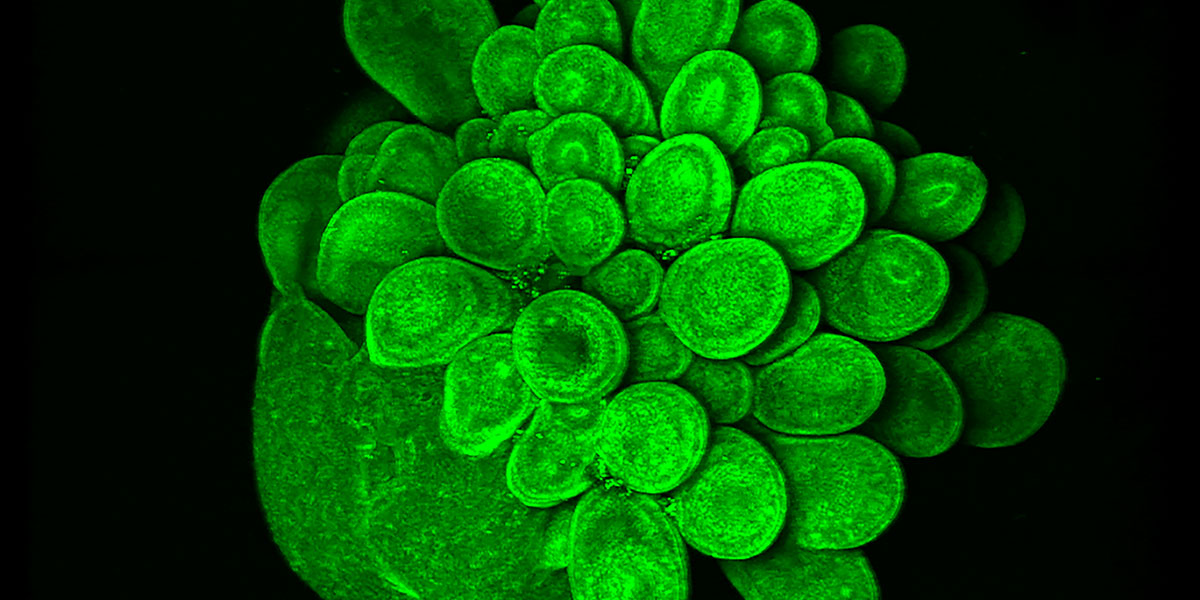

A Blooming Mini Brain

Mariana Oksdath Mansilla

Centre for Cancer Biology

This is an image of a 28 day-old human brain organoid, growing from iPSC that expressed Actin GFP. This 3D culture has a self-organisation of stem cells that mimics the fetal development of the human brain. To culture this organoid, we used a high-content scaffold that we developed in the lab using a 3D printer. The capability to print our high-content device, allows us to test efficiently several scaffold conditions for the growth of human brain organoids. The design of this human brain organoid array that generates healthy cultures (as we can see in the picture), is relevant in the search of a high-throughput platform for the screening of personalised treatment for brain cancer patients.